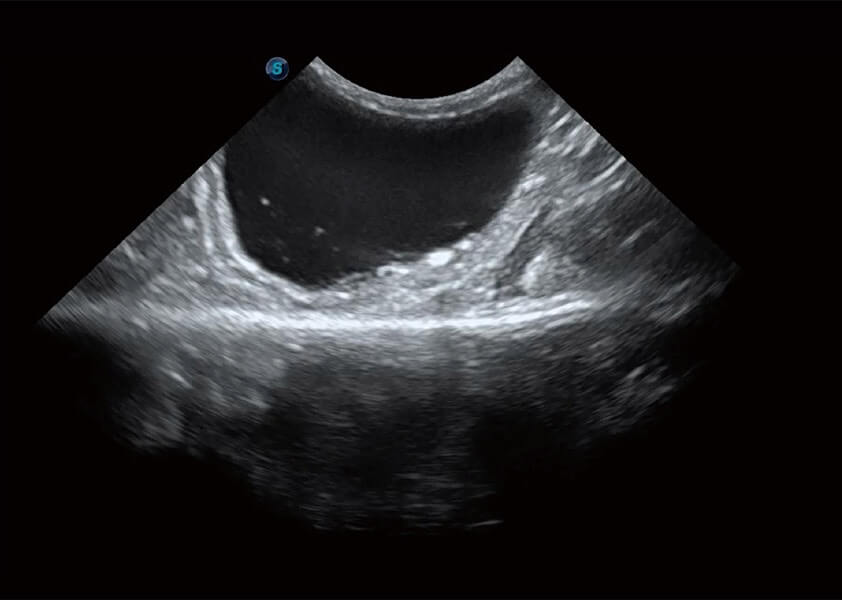

優(yōu)異的基礎(chǔ)圖像

(犬)膽囊泥沙

(貓)膀胱結(jié)晶